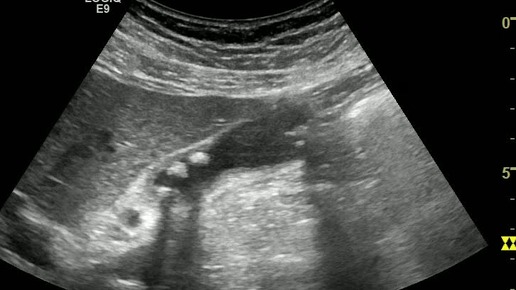

Ультразвуковые находки от врача УЗД Зорина Я.П.